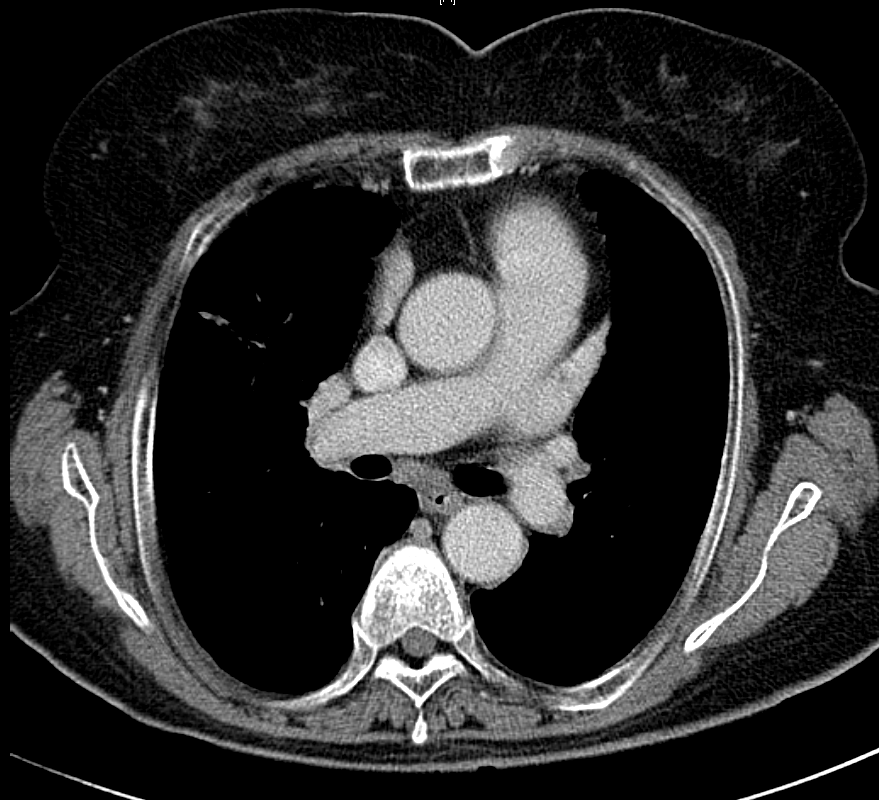

* CXR °ú  chest CT  »çÁøÀÔ´Ï´Ù.

¶Ñ·ÇÇÑ ¿µ»óÀ» À§ÇØ f/u Áß¿¡ ÂïÀº »çÁøÀ» ÷ºÎÇÏ¿´½À´Ï´Ù.

l  Chest CT

Progression of multiple small nodules in both lungs, along peri-BV and ILS, dominant on RUL and RML. No significant change of several small LNs in both hilar and mediastinum.   COPD: diffuse bronchitis. LH enlarge and PAH.